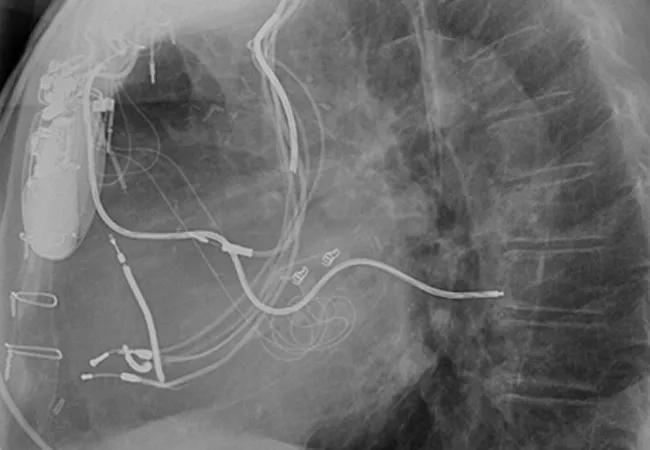

“Everything relevant to cardiovascular implantable electronic devices (CIEDs) is discussed on this site,” says Bruce Wilkoff, MD, Director of Cardiac Pacing and Tachyarrhythmia Devices at Cleveland Clinic, who spearheaded the website’s development.

With CIED technology proliferating, electrophysiologists are seeing a steady stream of patients presenting with broken or infected leads and devices. Yet the difficulties associated with conducting randomized controlled trials to evaluate these problems means that most studies are observational. This has left key issues such as risk stratification unaddressed.

Any physician can post a case or questions on LEADconnection.org and receive input from colleagues, notes Thomas Callahan, MD, another Cleveland Clinic electrophysiologist who is involved with the website’s operation. “Data show that lead extraction for infection is important and helpful, but is it always the best option?” he asks. “Are some high-risk patients better served with surgery or chronic antibiotic therapy? Which tools are best in specific scenarios? It’s important to have a community resource where we can talk about what works and doesn’t in our practices.”

“Lead extraction is potentially complicated and the procedures can be high-risk,” Dr. Rinaldi says. “Certain patients may have unusual anatomy or leads that are difficult to remove. In these cases it is useful to have perspectives from other practitioners on what could be a difficult decision, particularly if you don’t have a high degree of experience in such cases yourself.”